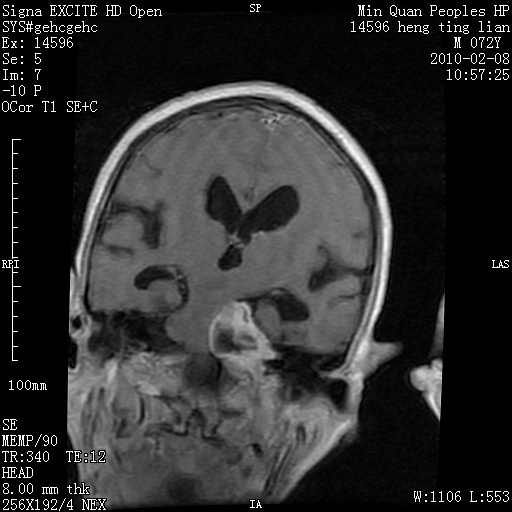

m,72,头疼,头晕两年,伴视力模糊三月,饮食呛咳两天。pe:颈部抵抗,左眼突出,左眼瞳孔约3mm,对光反射消失,双眼失明,伸舌困难,双肺呼吸音粗,心率110次/分,左上肢肌力i级,左下肢屈曲,肌张力高。现有08年2月19mri平扫及10年2月8日mri增强请会诊。ct病灶呈低密度伴散在点、片状等密度区,无明确钙化(无ct片资料可供上传)。[

脑外肿瘤,囊实性,环状不规则强化,内听道扩大,考虑神经源性肿瘤

左侧桥小脑区占位伴梗阻性脑积水----考虑 1神经鞘瘤 2室管膜瘤。

左侧桥小脑区神经鞘瘤伴梗阻性脑积水。

脑外肿瘤,病灶呈匍匐蔓延,表皮样囊肿可能性大。